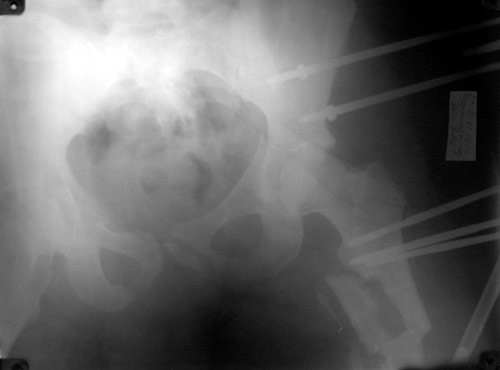

Уважаемые коллеги.Пациент 22 лет поступил 10.08.03. после ДТП. 11.08. жировая эмболия с суточной комой. В настоящее время в сознании, имеются невыраженные психические нарушения. Проводится скелетное вытяжение грузом 13кг.

В плане одномоментное вправление вывиха, наложение АВФ на бедро и скелетное вытяжение по оси и боковое за центральный отломок по оси шейки. Возможны ли варианты лечения в условиях ЦРБ?

Обсудили с коллегой Рунковым, нашим ведущим специалистом по травме таза и вретлужной впадины - здесь однозначно нужно делать открытый остеосинтез вертлужной впадины. Возможно, и лонного сочленения. Для уточнения положения лонно-седалищного фрагмента надо inlet проекцию.

Если этот фрагмент сильно не развернут, есть шанс на закрытое вправление впадины с помощью резьбового стержня, введенного сквозь нижний полюс головки в медиальную стенку впадины. Но шанс этот не сильно велик, поэтому попытку лучше проводить в условиях, позволяющих тут же перейти к открытому остеосинтезу. Для него, в свою очередь, нужны условия - и хирург с необходимыми навыками, и специальные инструменты и имплантаты.

То, что получилось в приложении. Стоит ли дальше тянуть головку винтами или низводить проксимальный отломок по оси?

Уважаемый Борис! Я не имел возможности ознакомиться с рентгенологической картиной сразу после травмы. Имею картинку на данный момент (Ваше приложение). Считаю, что Вы имеете право оставить всё в имеющемся состоянии, но желательна дополнительная дистракция по оси шейки бедренной кости. Далее стабилизировать аппарат. Артроз больному обеспечен, сроки наступления его декомпенсации известны только аллаху.

Можно только порадоваться за пациента и врачей, положение отломков значительно улучшилось. Может быть, удастся добиться "вторичной конгруэнтности" даже при сохраняющемся диастазе на уровне перелома. Из того, что видно - стержней в тазу маловато, лучше бы зацепиться за гребни подвздошных костей (по 3-4 стержня), тогда можно будет пациента и поднять на костыли.

Возможно, и то, и другое. По одной прямой проекции ситуацию не оценить - желательно сделать косые проекции (Judet) левой вертлужной впадины, на которых будет видно, конгруэнтна ли головка со сводом, не надо ли подвинуть ее кпереди или кзади.

По бедру - ось (по одной проекции) и длина восстановлены. Непривычно выглядит стержень с медиальной стороны, мы обычно обходимся только

наружной полуокружностью бедра. Если аппарат здесь предполагается как окончательный фиксатор - похоже, это надолго...

На первый взгляд репозиция вертлужной впадины не плохая, однако следует сделать проекционные снимки по Judet, а вот аппрат конечно подкачал, да и больного жалко. Былобы красиво сейчас после рентген-контроля перкутанно ппровести стягивающие винты через перелом вертлужной впадины из подвздошной в лобковую и из седалищной в подвздошную. А бедро заштифтовать, а потом снять аппарат и отпустить больного, передний отдел возможно фиксировать АВФ.